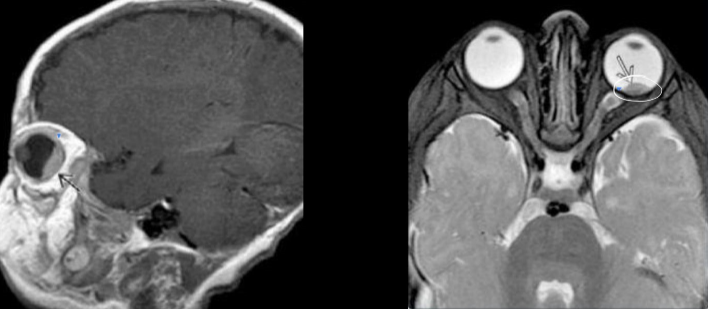

Retinoblastoma

Tumor maligno primario de la retina

- Trilateral: bilateral + t. neurplastico (g. pineal)

- Cuadrilateral: bilateral + t. pineal y region supraselar

- Clx: leucocoria - pupila blanca

Estudio de imagen retinoblastoma

Calcificaciones intraoculares

- TC: ver calcificaciones

- RM: mapeo del tumor

- US: ultima opcion si no hay tc o rm